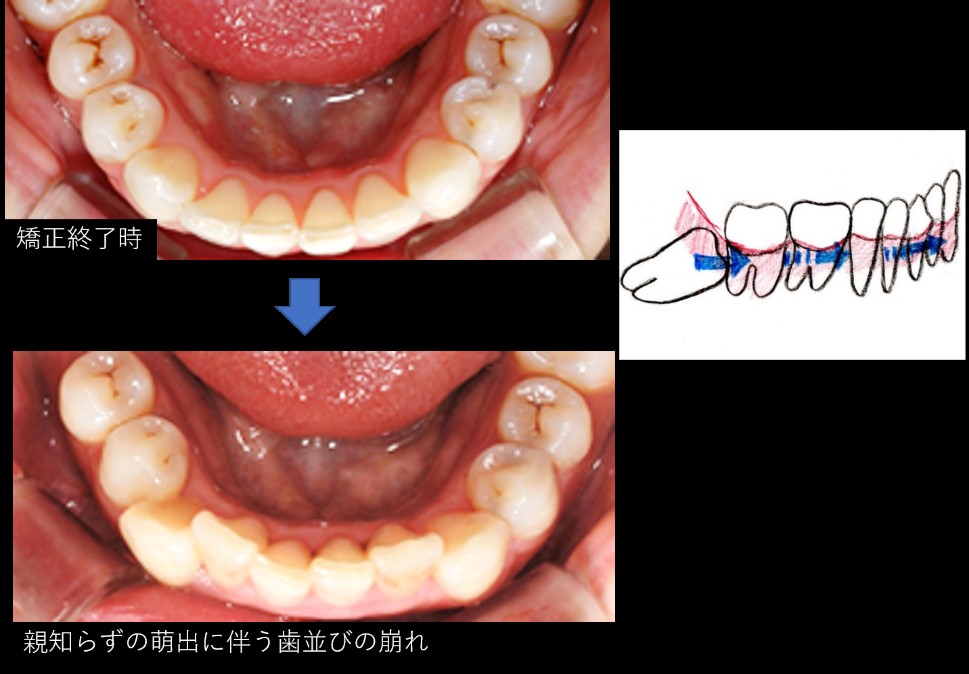

親知らずが生えて歯並びが悪くなった 健勝会こうづま歯科医院 ローズ歯科医院症例ブログ

親知らずのせいか歯並びが悪くなりました 26歳の男です 昔は誰からも歯並 Yahoo 知恵袋

11年の歯科矯正が台なしになった女性の悲劇 定期検診に加え 親知らずの積極抜歯 が大切

写真あり 歯並びが悪くなった原因は歯周病か親知らず抜歯のせい 歯チャンネル歯科相談室